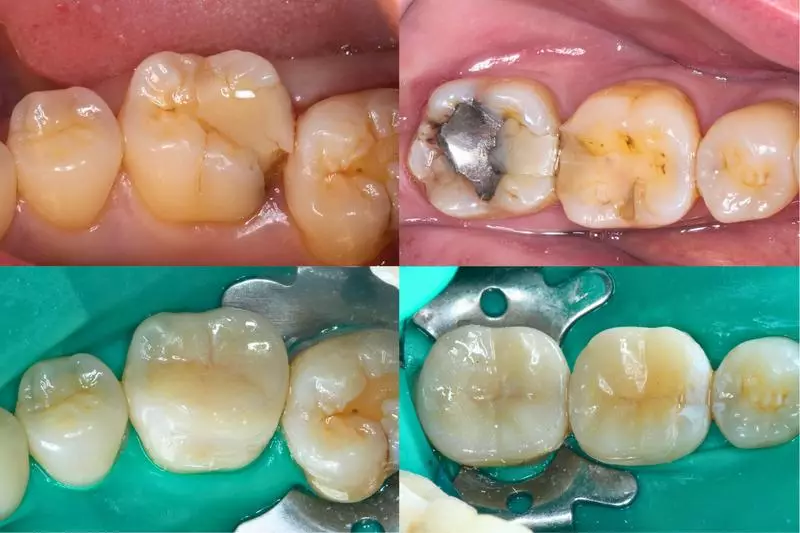

傳統樹脂填補下二次蛀牙並造成牙冠斷裂(左上)陶瓷嵌體修復後(左下)

臨床常見銀粉與牙齒間微滲漏(右上)陶瓷嵌體修復後(右下)